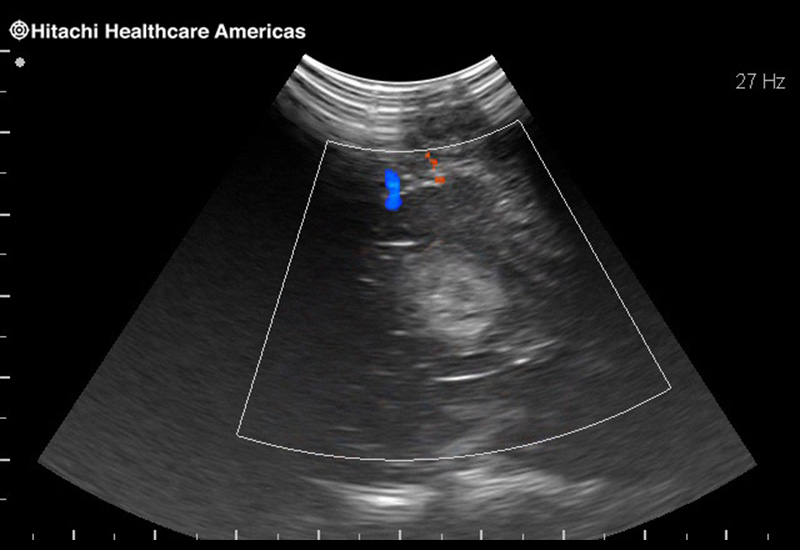

Superior guidance for all applications

Fujifilm Healthcare Americas is committed to designing tools that help surgeons navigate inside the human body and provide the necessary information to immediately make critical surgical decisions.

Fujifilm Healthcare's dedication to Surgeons provides outstanding ultrasound technology, professional support and the specialized tools necessary to best perform comprehensive real-time ultrasound imaging in Breast Surgery, General Surgery, Laparoscopic Surgery, Neurosurgery, Robotic Surgery and Surgical Oncology.

Fujifilm Healthcare’s ARIETTA Precision features state-of-the-art digital architecture and advanced imaging technologies to redefine the capabilities of surgical ultrasound.

Fujifilm Healthcare’s ARIETTA Precision features state-of-the-art digital architecture and advanced imaging technologies to redefine the capabilities of surgical ultrasound.